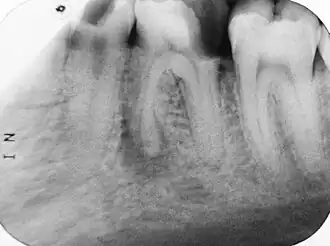

Предложенная Vertucci классификация относится к каждому отдельному корню, поэтому в различных корнях многокорневых зубов могут встречаются любые комбинации типов. Следует подчеркнуть, что данная классификация даёт весьма грубую и приблизительную схему возможных вариантов систем корневых каналов. Таким образом, представленные схемы на практике могут отличаться вариабельностью, встречаться в разных комбинациях, создавая весьма сложную топографию системы корневых каналов. Особую настороженность должны вызывать у клиницистов случаи наличия множественных апикальных отверстий, имеющие немаловажное значение в возникновении возможных осложнений после проведения эндодонтического вмешательства[3]. Именно поэтому практикующие врачи-стоматологи перед началом процедуры депульпирования проводят рентгенографическое обследование, позволяющее достоверно определить тип и количество корневых каналов в зубе[2].

- витальная экстирпация — при отсутствии выраженных воспалительных явлений, переходящих в периодонт, удаление сосудисто-нервного пучка и его обтурация проводится под анестезией в одно посещение. В канале оставляют лекарство (для антисептики и снятия воспаления). В процессе лечения необходимо сделать как минимум 2 рентгеновских снимка: первый — до начала лечения (для оценки длины и структуры каналов), а второй — после (для оценки качества пломбирования каналов).